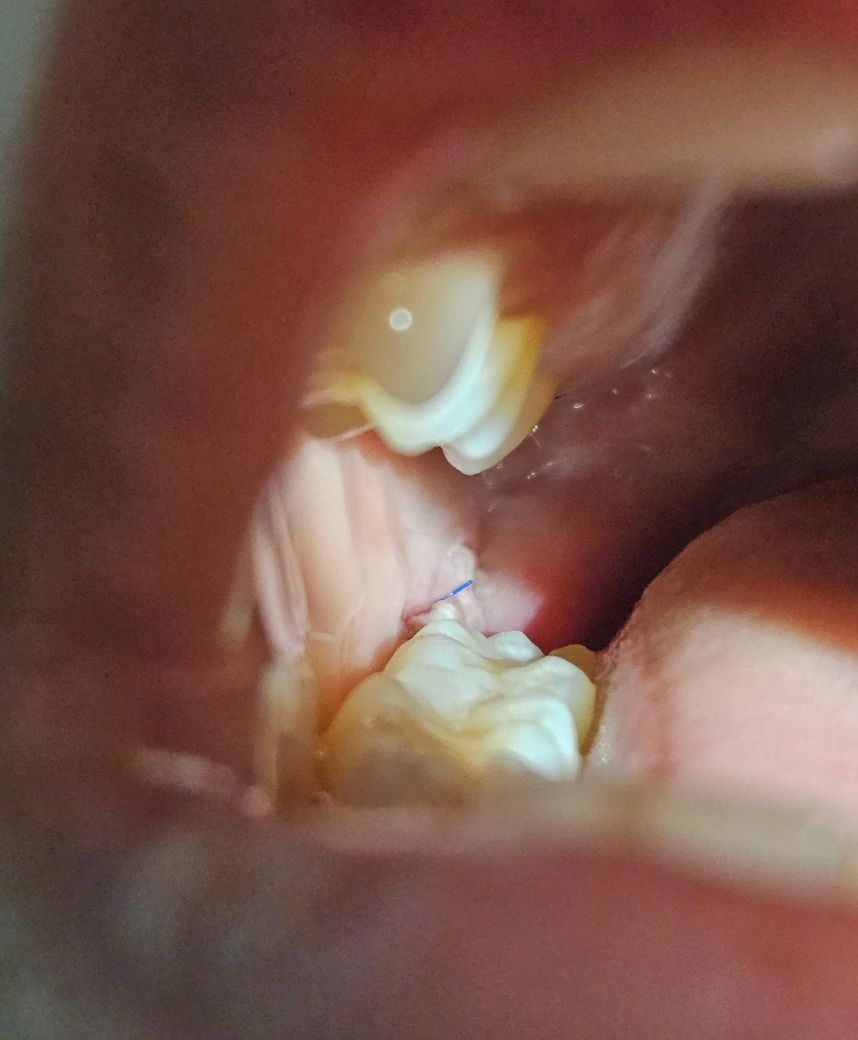

사랑니 발치 후 잘 아물고 있는건가요?

사랑니 발치 후 3일차인데 자다가 피떡이 사라지고

하얗게 올라와있어요ㅠㅠ

음식물 또는 염증일까요?

아니면 잘 아무는 중인가요

밥알이 낀 거 같기도 하네요..

사진 상 큰 문제는 보이지 않습니다. 음식물 끼임 등에 대해서 관리만 조금 더 잘해주시면 됩니다.

사진으로 보기에는 큰 문제없이 치유중인 것으로 보입니다. 걱정하지는 않으셔도 되겠고 혹여 통증이 점차 심해진다거나 볼이나 턱쪽이 부어오르는 경우에는 치과에 내원하시면 되겠습니다.

사진상으로 보면 크게 문제 없이 잇몸이 잘 아물고 있으니 음식물이 남지 않도록 잘 헹궈주시는게 좋습니다.

염증 육아조직으로 발치후 치유과정에서 생기게 됩니다 해당부위 음식물끼어있지 않게 가볍게 물로 헹궈주세요

사진으로만 봤을 경우에는 크게 문제가 없이 아물고 있는것으로 보입니다.